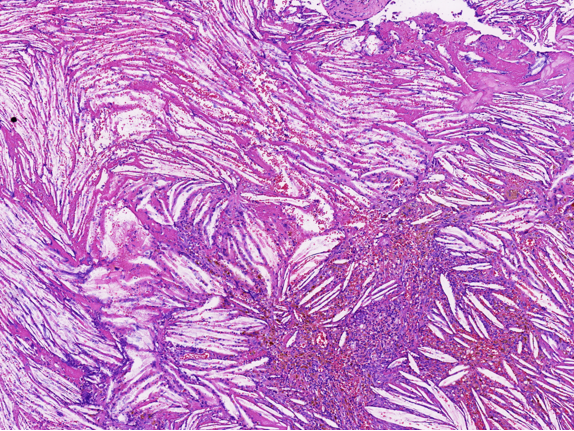

病理特征:宽薄乳头、 迷宫样内翻生长、单一肿瘤细胞形态、棘层松解、显著中性粒细胞浸润;

可见:细胞旋涡、透明细胞变、微囊形成、黏液纤毛上皮帽、部分肿瘤细胞异型性增加、坏死。